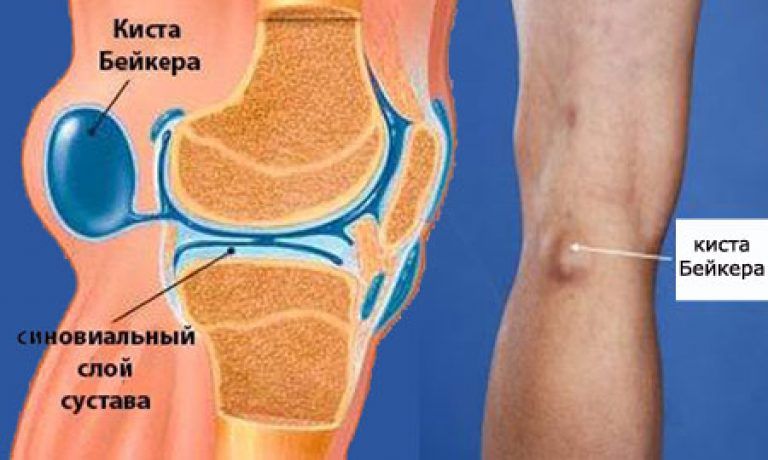

Фото и диагностика кисты Бейкера